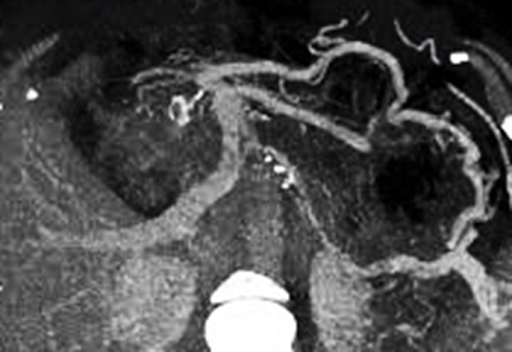

CT Imaging (Preferred Modality)

• Shows a filling defect in the splenic vein.

• Often reveals associated pancreatic pathology such as inflammation or mass.

• May demonstrate collateral veins and splenomegaly.

Featured Case Image:

The attached contrast-enhanced CT image demonstrates an occlusive thrombus in the splenic vein with surrounding pancreatic inflammation, consistent with pancreatitis-induced SVT.